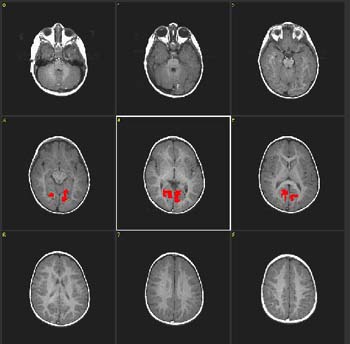

| Paciente |

Niño de 4 años de edad con autismo

ACTIVADO: Presentación de luces intermitentes a 8 Hz, con gafas especiales colocadas

DESACTIVADO: Nada. Paciente sedado con nembutal |

0,000002 |

4,0 |

| Activación |

Cortes coronales. Las áreas coloreadas en la figura se obtuvieron restando ACTIVADO a DESACTIVADO. Por consiguiente, el resultado muestra "desactivación", lo que representa la hiperextracción de oxígeno en las áreas visuales primarias (V1). Este hallazgo aparece constantemente en niños pequeños, ya sea despiertos o bajo sedación. |